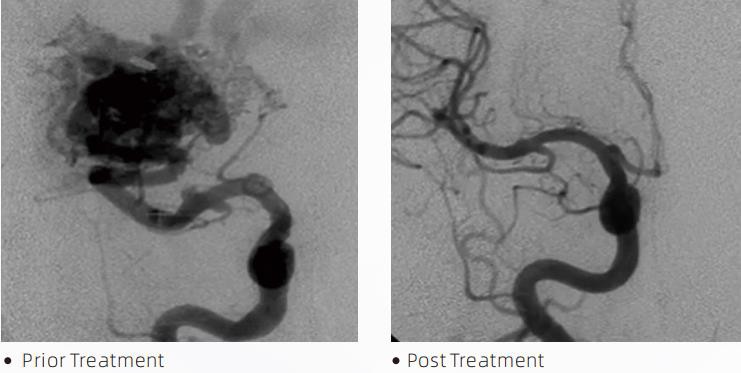

LavaTMLiquid Embolic System je interventna endovaskularna terapija za liječenje cerebrovaskularnih malformacija. Cerebrovaskularna malformacija odnosi se na skupinu benignih ili malignih neurovaskularnih abnormalnosti koje mogu dovesti do intrakranijalnog krvarenja, cerebralnog infarkta, cerebralne ishemije i drugih bolesti. Sustav tekuće embolizacije medicinski je uređaj koji se primjenjuje jednostavnim intravaskularnim umetanjem, a koji embolizira abnormalne cerebralne krvne žile ubrizgavanjem posebnog tekućeg materijala. Tekući materijal stvara kontroliranu tkivnu emboliju unutar krvnih žila, što može smanjiti utjecaj cerebrovaskularnih malformacija na pacijente. Mikrokateter kompatibilan s DMSO koji je indiciran za upotrebu u neurovaskulaturi koristi se za pristup mjestu embolizacije. Lava tekući agens za emboliju je neadhezivni sustav tekućih emboličkih agenasa koji se sastoji od kopolimera EVOH (etilen vinil alkohol) otopljenog u DMSO (dimetil sulfoksidu) i suspendiranog mikroniziranog tantalovog praha za pružanje kontrasta za vizualizaciju pod fluoroskopijom. LavaTMdostupan je u tri formulacije proizvoda, LAVA-12, LAVA-18 i LAVA-34. LAVA-12: Preporuča se pri hranjenju distalnih mikro žila i kroz male hranilice. LAVA-18: Preporuča se kada će se injekcije hranjenja peteljke provoditi blizu čvorišta; LAVA-34: Preporučuje se za embolizaciju većeg protoka i većih fistuloznih komponenti.